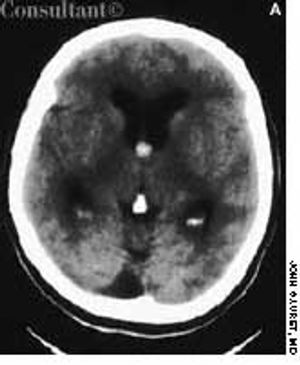

After suffering with recurrent, diffuse, daily headaches for 4 months, a 51-year-old woman sought medical advice. She described the headaches as severe and said they were affected by the position of her head, particularly when bending forward. She also reported episodes of transient numbness on her right side. No syncope was noted, and the patient denied nausea and vomiting.